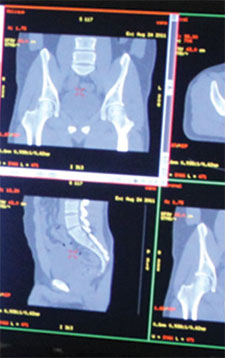

Se puede considerar a la radiología digital como el mayor avance tecnológico en sistemas de imágenes de uso médico de la última década. En pocos años, la película fotográfica para rayos X podría caer completamente en desuso. Una analogía apropiada y fácil de entender es la substitución de las cámaras fotográficas tradicionales por las cámaras digitales. Las imágenes se pueden obtener, borrar, modificar y, a continuación, se pueden enviar a una red de computadoras.

Los beneficios que aporta la radiología digital son enormes. Mediante esta técnica se puede llegar a prescindir completamente de las placas de Rayos X convencionales. El médico que ordenó el examen puede ver en su computadora la imagen que solicitó, e incluso emitir un informe pocos minutos después de haberse realizado la imagen. Las imágenes ya no se guardan en un único lugar, sino que varios médicos situados a kilómetros de distancia las pueden ver simultáneamente.